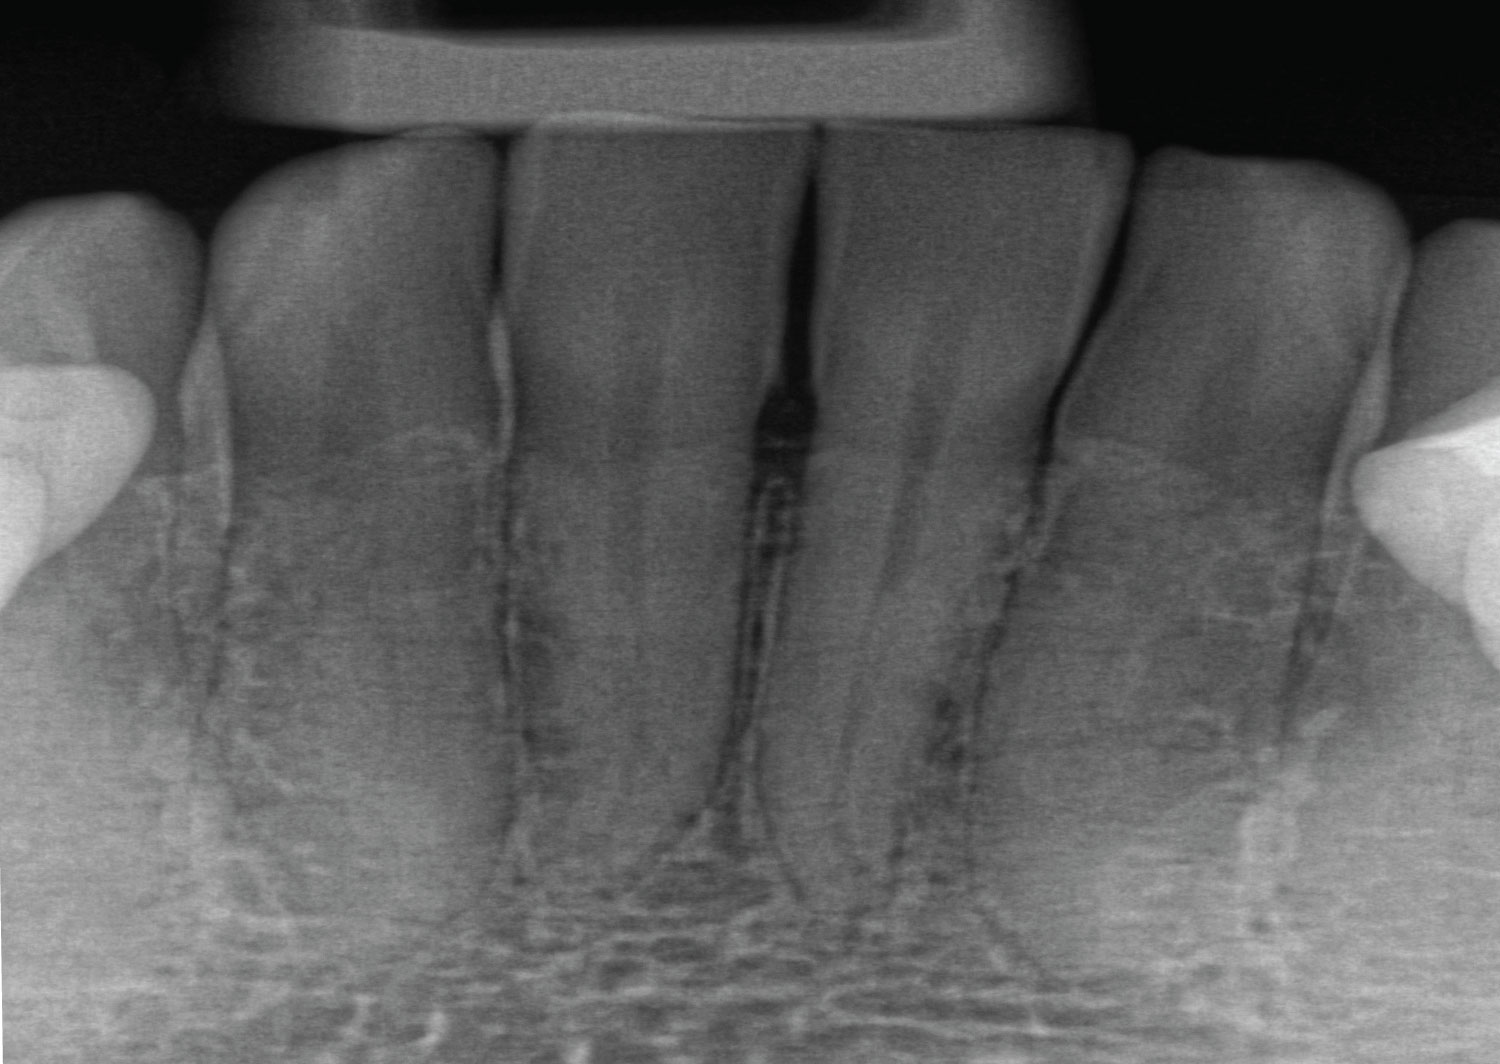

Davis CA Family Dentist Cavities in real life and in Xrays James W What Can Dental X Rays Detect This is useful, as your dentist can recommend certain treatments (for example, braces, implants, or wisdom teeth removal) based on your results. Show areas of decay that may not be visible. The size and location of the sensor placement are a big factor in how comfortable or uncomfortable you will be. What Can Dental X Rays Detect.

Digital Dental XRays Coppe + Sears Lexington Pediatric Dentistry What Can Dental X Rays Detect The size and location of the sensor placement are a big factor in how comfortable or uncomfortable you will be. Show areas of decay that may not be visible. This is useful, as your dentist can recommend certain treatments (for example, braces, implants, or wisdom teeth removal) based on your results. What Can Dental X Rays Detect.

Dental XRays Adelaide Azura Dental What Can Dental X Rays Detect The size and location of the sensor placement are a big factor in how comfortable or uncomfortable you will be. Show areas of decay that may not be visible. This is useful, as your dentist can recommend certain treatments (for example, braces, implants, or wisdom teeth removal) based on your results. What Can Dental X Rays Detect.

Dental Xrays Why, Which, & When? Digital Xrays Charlotte dentist What Can Dental X Rays Detect Show areas of decay that may not be visible. This is useful, as your dentist can recommend certain treatments (for example, braces, implants, or wisdom teeth removal) based on your results. The size and location of the sensor placement are a big factor in how comfortable or uncomfortable you will be. What Can Dental X Rays Detect.